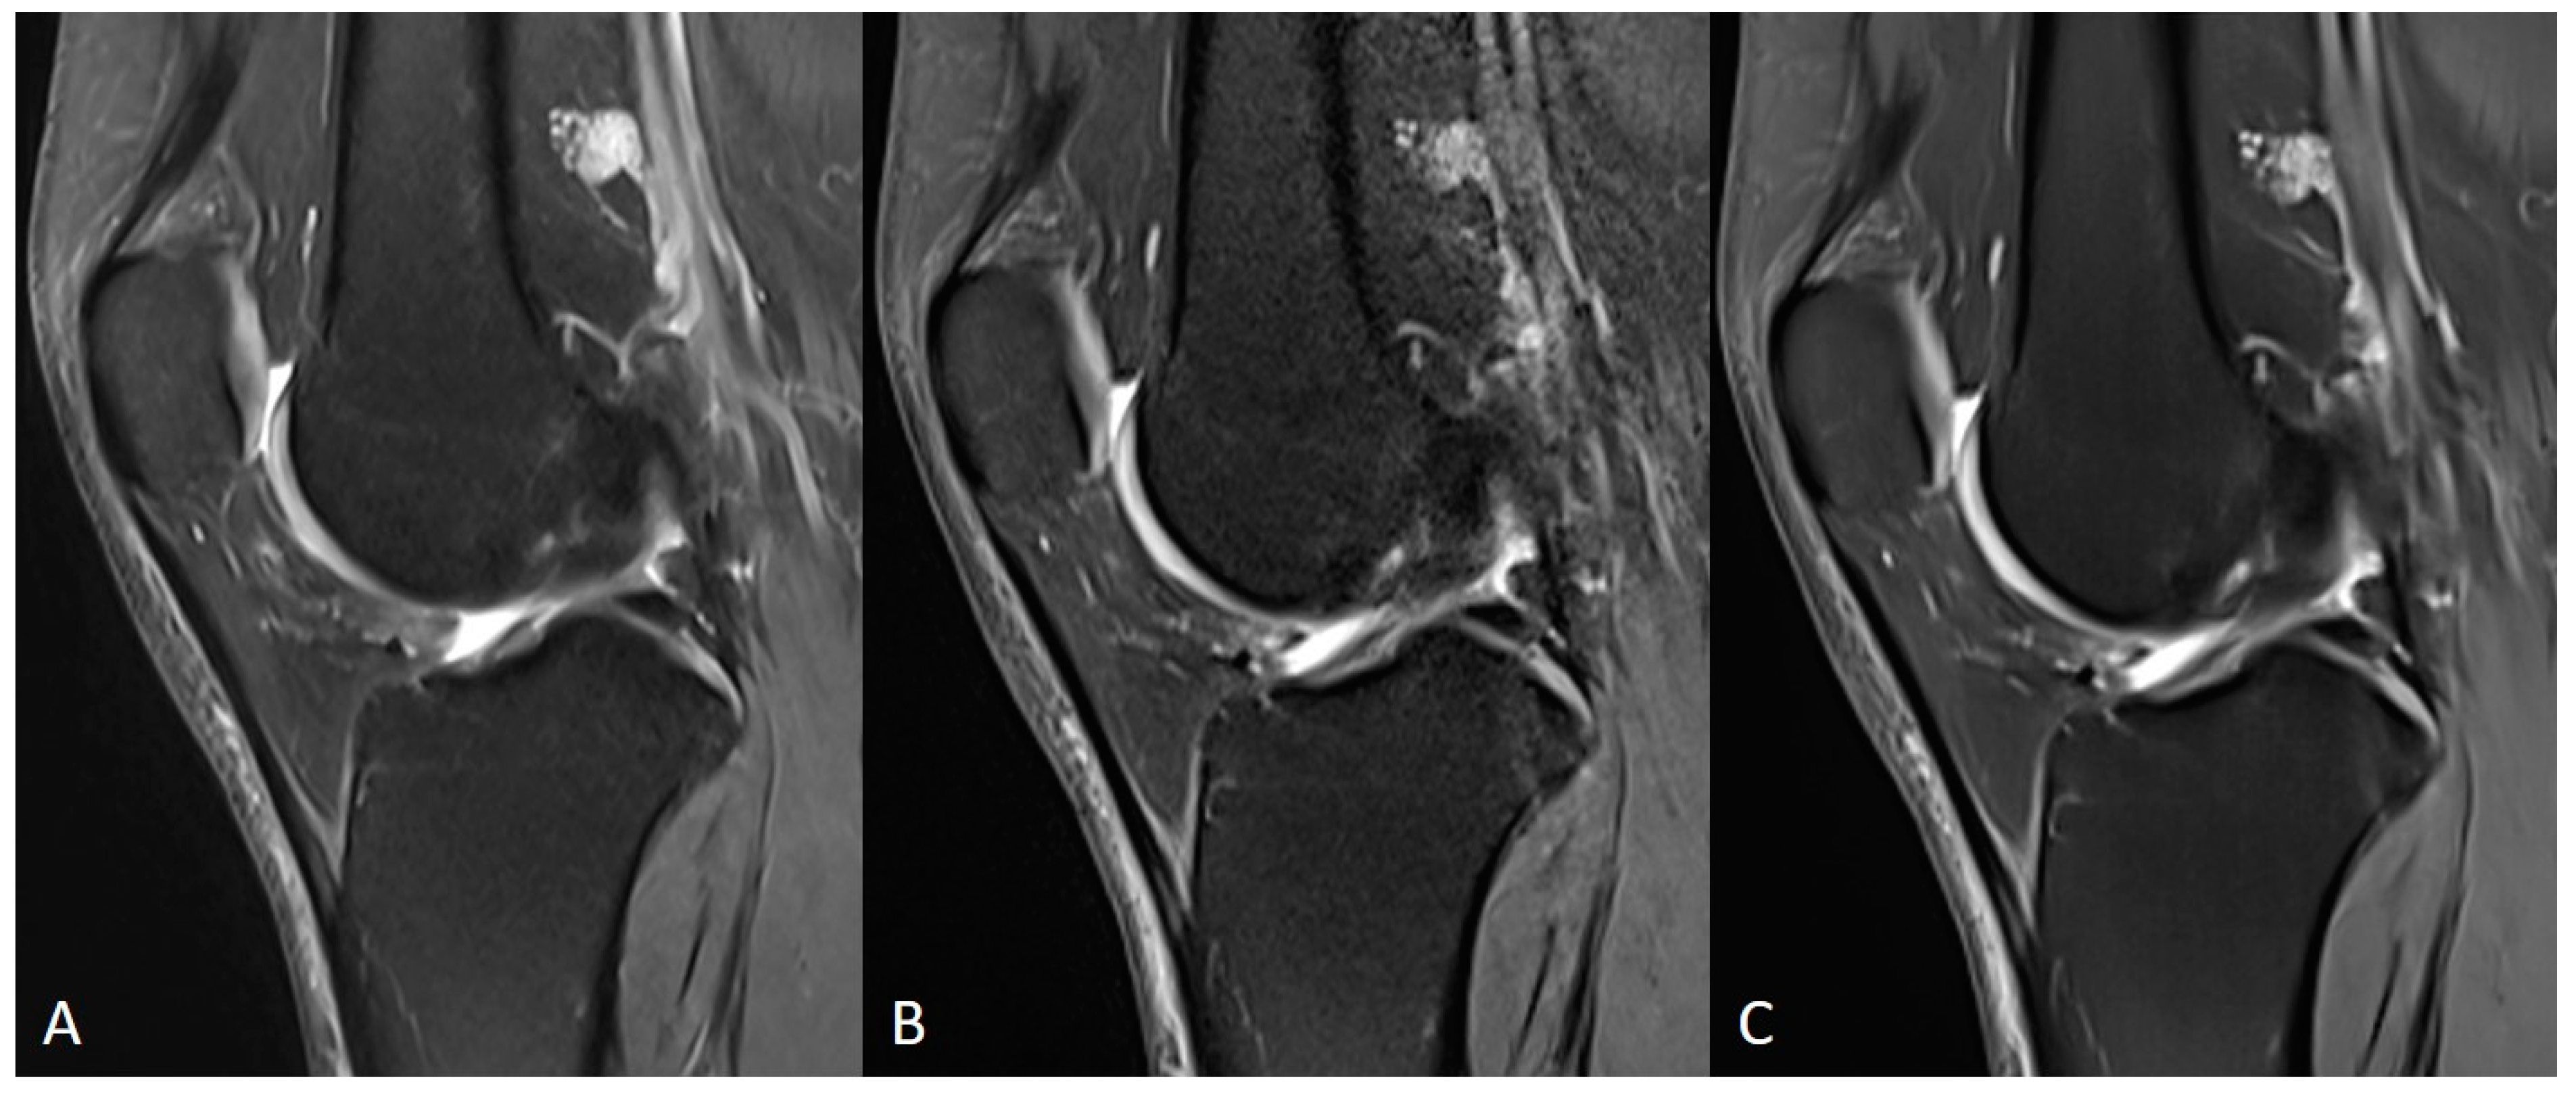

3.1. Assessment of Image Quality

3.2. Assessment of Anatomical Structures